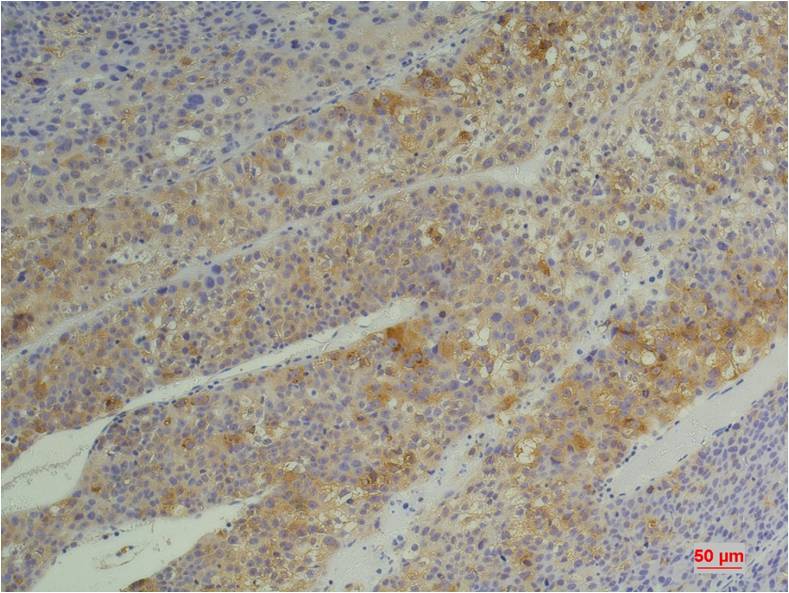

Immunohistochemical analysis of paraffin-embedded Human Heptacarcinoma using?Cyclophilin B(EM1219)Mouse mAb diluted at 1:200.

Immunohistochemical analysis of paraffin-embedded Human Pancreatic Carcinoma using?Cyclophilin B(EM1219)Mouse mAb diluted at 1:200.